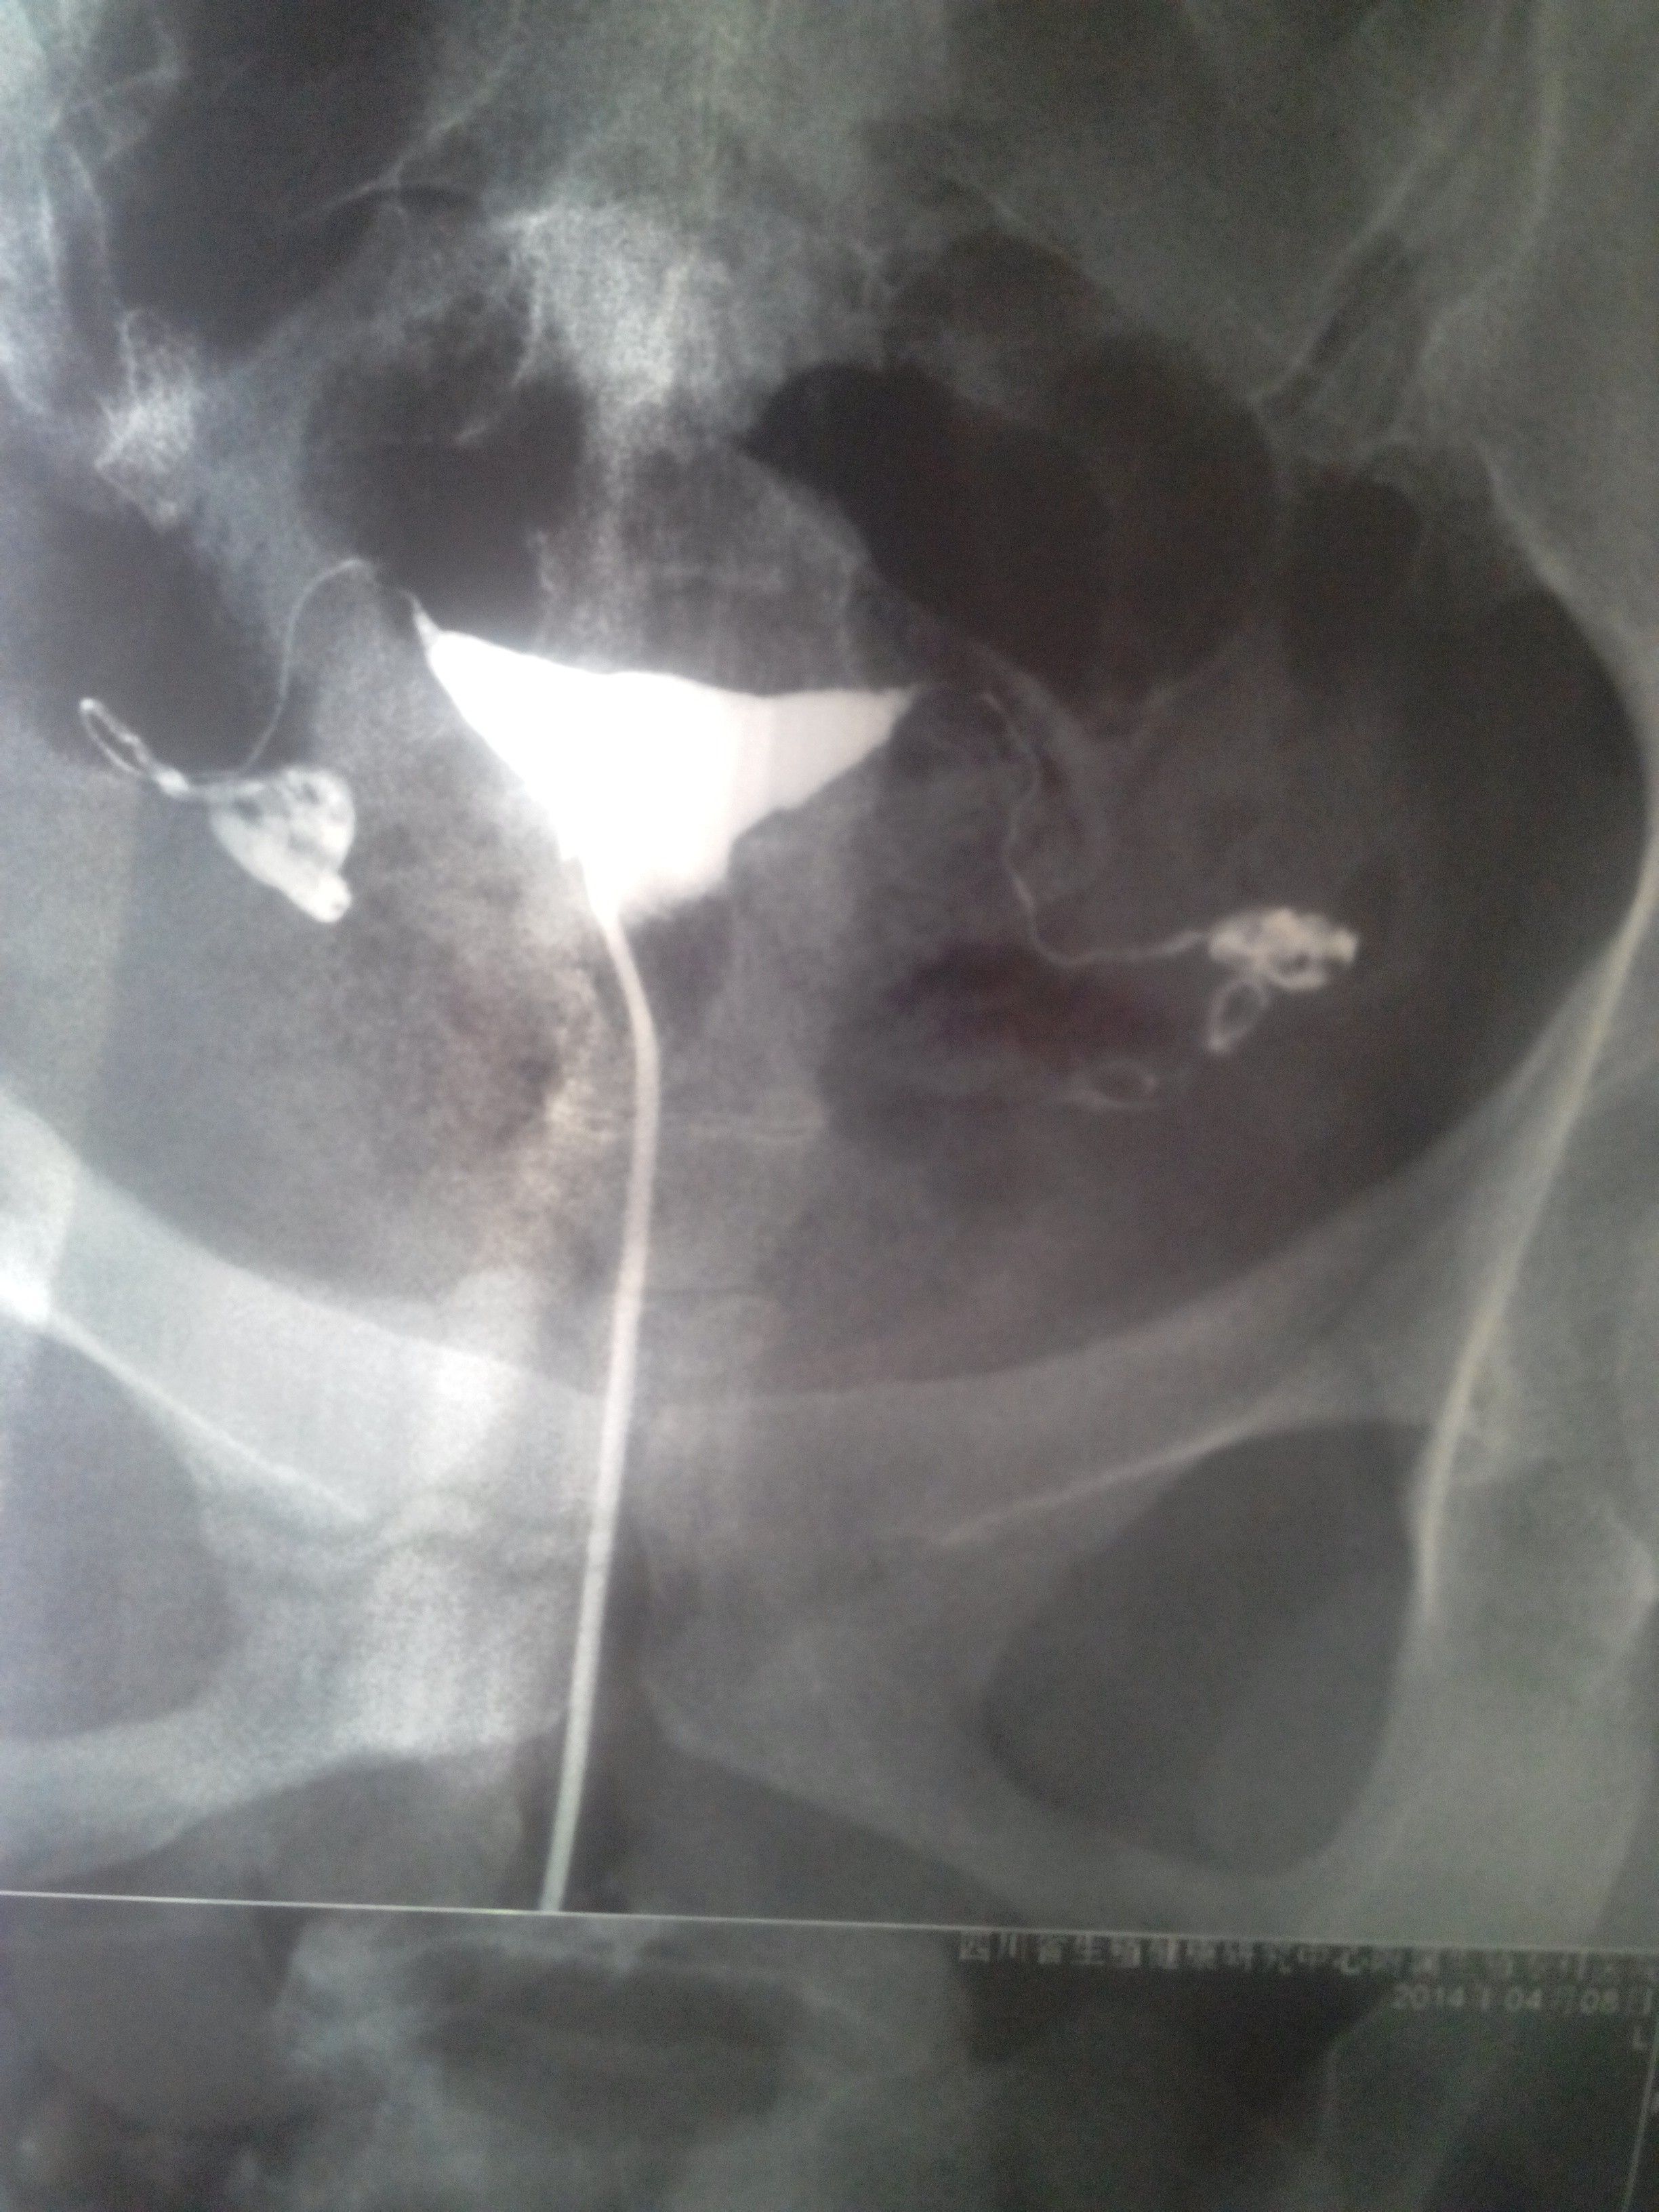

你好 我昨天造影做了输卵管 医师说我的输卵管不是很好 要求我做手术 可我不知道该怎么办 请人分析哈 谢谢 点击展开 匿名用户 2014-04-09 16:37 为您推荐: 其他回答 病情分析: 您的检查看右侧输卵管通而不畅。左侧输卵管积水,要及时观察,这种情况有可能造成宫外孕 指导意见: 要及时观察,必要的情况下最好及时手术治疗,避免影响正常的怀孕 匿名用户 2014-04-09 16:43 相关问题 医生,你好 我想要一个孩子,医生先让我做了输卵管碘造影,结果是通而不畅,而且输卵管下垂我已经… 你好,我是6月30日例假,打算7月5日去做输卵管造影,后来查出来有霉菌,没做成,医生给我开了治疗霉 你好,我是6月30日例假,打算7月5日去做输卵管造影,后来查出来有霉菌,没做成,医生给我开了治疗霉